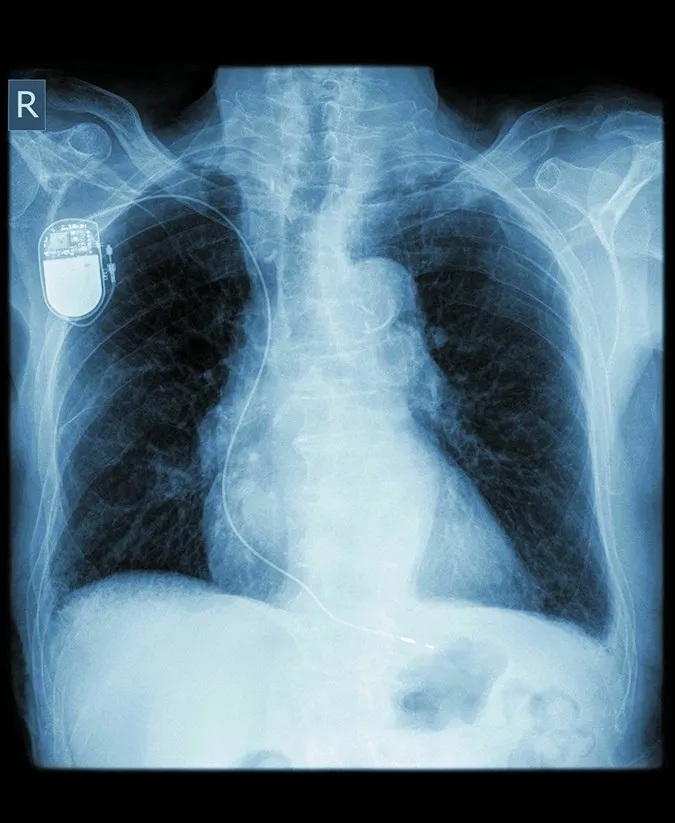

Improvements in technology and greater patient adherence to heart-healthy lifestyles are allowing individuals with implantable cardioverter defibrillators (ICDs) to live longer with their cardiac devices. ICDs are implanted in the chest and have thin wires (called leads) that extend into the heart to deliver small electric shocks when the heartbeat gets out of rhythm. But having an ICD for decades means youre at a higher risk for potentially serious complications, compared with patients who have an ICD for a shorter period.